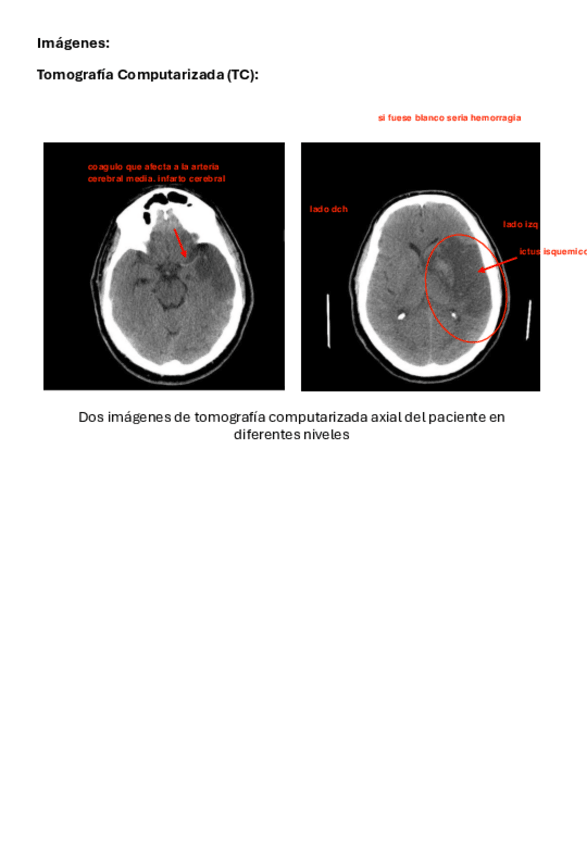

Nervioso-2-ICTUS.pdf

T2.2-ICTUS.pdf